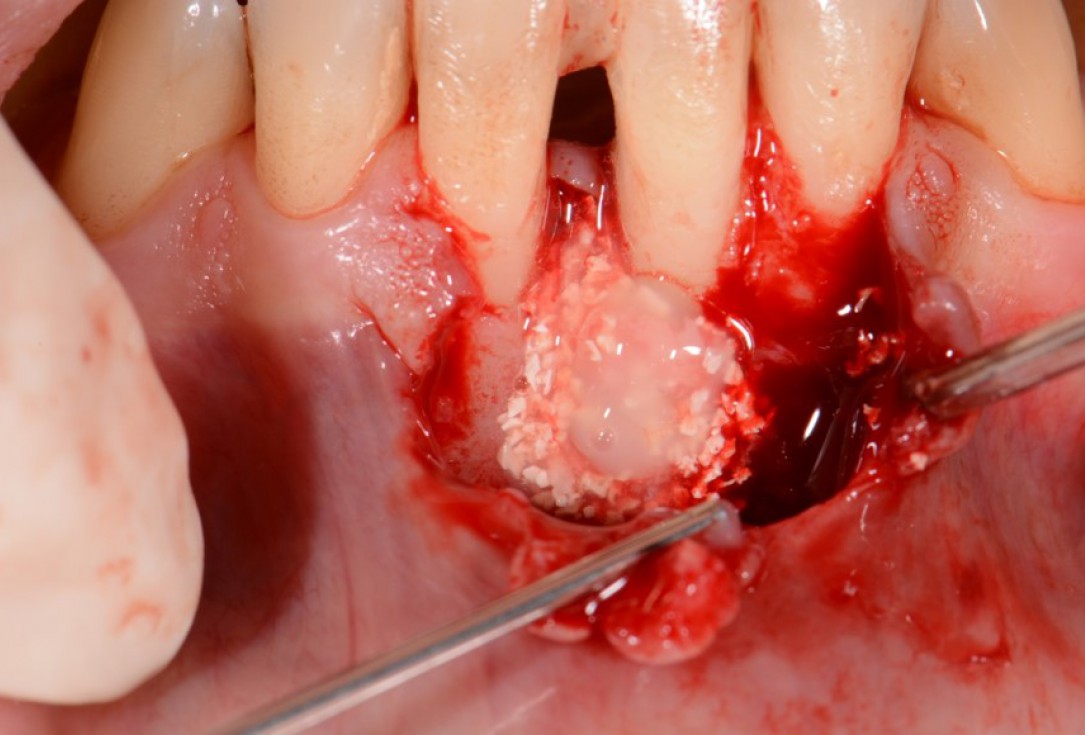

05/12 - Application of small cerabone® granules mixed with Straumann® Emdogain®.Two-wall intrabony defect treated using cerabone® and Straumann® Emdogain® - Dr. D. Rakasevic & Prof. Dr. S. Jankovic